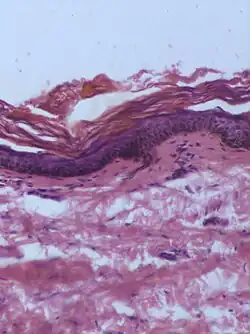

| Dysplastic nevus | Usually a compound nevus with cellular and architectural dysplasia. Like typical moles, dysplastic nevi can be flat or raised. While they vary in size, dysplastic nevi are typically larger than normal moles and tend to have irregular borders and irregular coloration. Hence, they resemble melanoma, appear worrisome, and are often removed to clarify the diagnosis. Dysplastic nevi are markers of risk when they are numerous, such as in people with dysplastic nevus syndrome. According to the National Institute of Health (NIH), doctors believe that, when part of a series or syndrome of multiple moles, dysplastic nevi are more likely than ordinary moles to develop into the most virulent type of skin cancer called melanoma.[19] | ![]() In this case, the central portion is a complex papule, and the periphery is macular, irregular, indistinct and slightly pink. |

Characteristic rete ridge bridging, shouldering, and lamellar fibrosis. H&E stain.

|